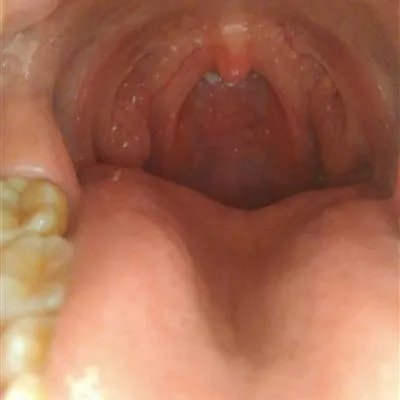

概述舌头根部有肉疙瘩可能是炎症导致的,必须及时的检查治疗,一般是由于咽部的炎症刺激引起,如果你没有症状的话,可以不予特殊治疗,不严重的,即使输液,淋巴滤泡也不会完全消退,必要时可以考虑微波治疗,下面给大家介绍下舌根有疙瘩是怎么回事?舌根有疙瘩是怎么回事1第一:舌根有疙瘩不疼不痒的话是不需要特殊的进行治疗的,可能是轮廓乳头组织导致的,平时加强日常生活调养,保持心情舒畅,练达豁达乐观的心态和性格;生活要有规律,起居有常,保证足够的睡眠;加强体育运动锻炼,早晨跑步晚上散步;劳逸结合,避免疲劳。2第二:舌根长疙瘩,多数是由于体内虚火过旺等原因,造成的上火所引起的。还有一部分是由于舌根发炎,咽喉炎等炎症所引起的,如果症状一般,在能控制的范围内

3第三:舌根长疙瘩是舌头的慢性炎症长期刺激导致舌乳头角质化,引起咽腔一系列不时地感觉,如咽部异物感,毛糙不适,有时刺痛,微觉咽干咽痒疼痛,检查可见舌根扁桃体表面散布糙米状小粒,尖端细小,根底牢固,质地坚硬,不易剥下,剥下后遗留轻度出血点,周围粘膜不出血。